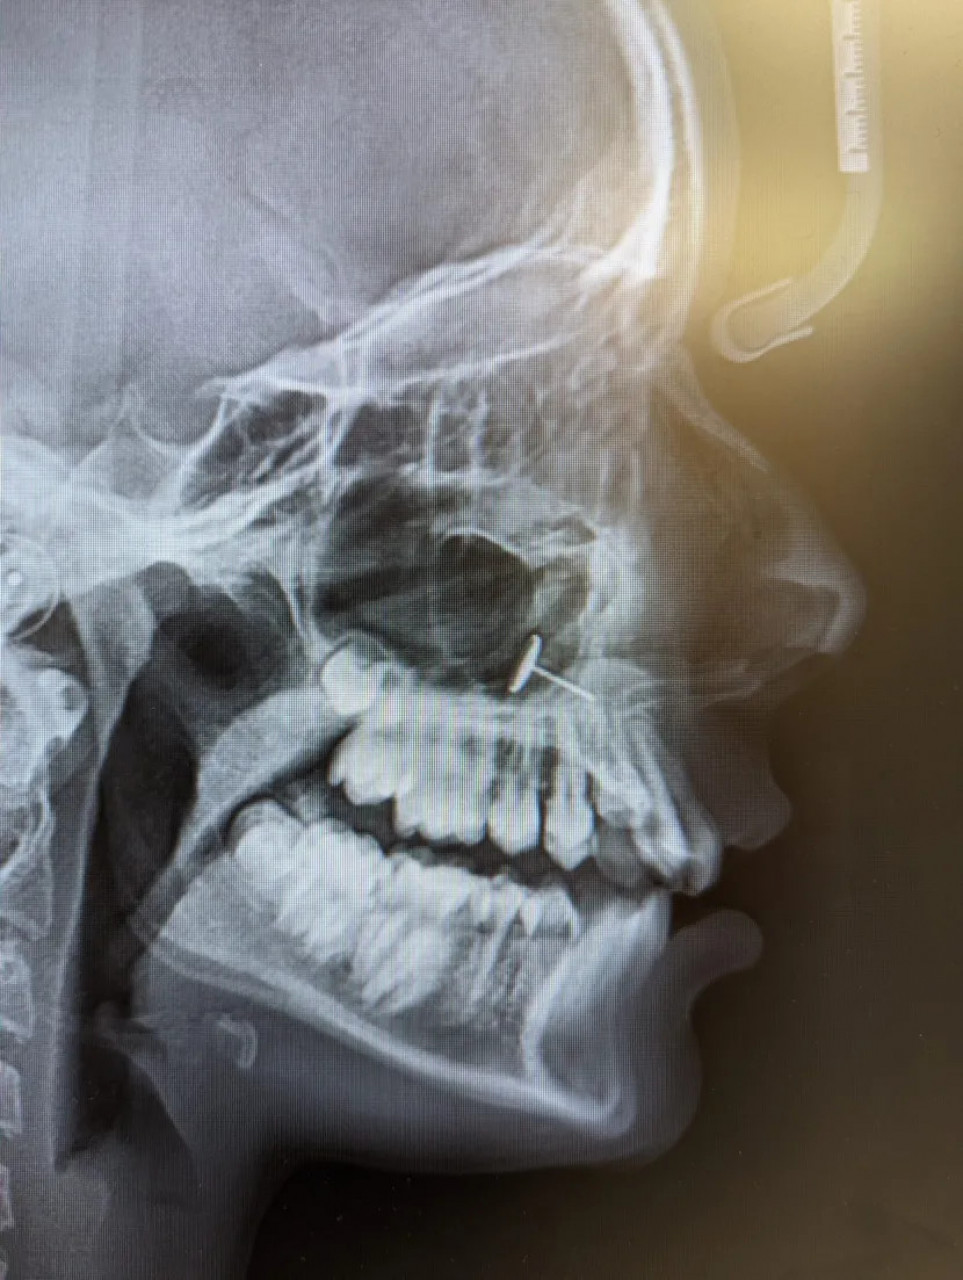

“Зубар се вратио са рендгенским снимком и сви смо неколико минута покушавали да схватимо шта гледамо”, рекла је мајка.

На снимку се јасно видео комад метала заглављен у синусима тинејџерке(!), али мајка није умела да објасни како је тамо доспео. Истину је знала девојчица, али је ћутала.

Све би остало скривено, да није било прегледа код зубара. Мајка је објавила рендгенски снимак на Редиту који је брзо постао виралан.